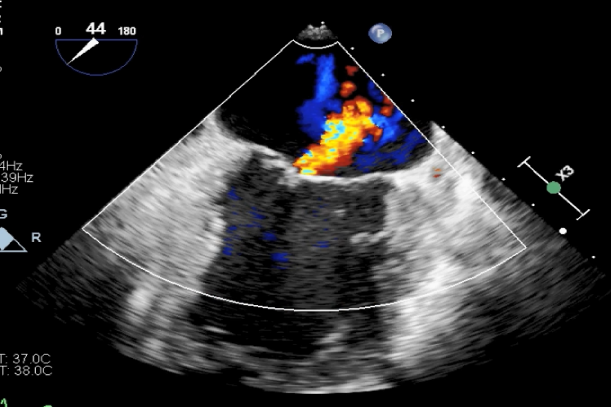

麻醉状态下TEE显示中大量返流MR:

患者麻醉方式采取全麻,建立静脉通路后,穿刺右侧股动脉以及股静脉,预埋ProGlide缝合器,冠脉造影复查提示支架通常。TEE超声指导下经房间隔穿刺后进入左房,送入鞘管,MitraClip调整后顺利到达二尖瓣目标位置,后在X线及食道超声辅助下,使用1枚XTR二尖瓣夹准确夹合二尖瓣A2-P2区,超声即刻测反流面积明显减少,LVOT切面,四腔心切面以及3D下证实夹合组织充分,患者收缩压由术前的108/62mmHg上升至130/72mmHg,左心房压力显著减低,肺静脉多普勒波形由反向恢复正常。手术顺利结束,安返普通病房。

XTR夹子释放,返流明显减少